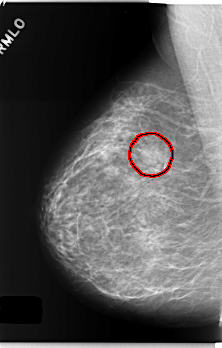

C_0240_1.RIGHT_MLO

RIGHT_MLO LINES 5904 PIXELS_PER_LINE 3760 BITS_PER_PIXEL 12 RESOLUTION 50 OVERLAY

FILE: C_0240_1.RIGHT_MLO.OVERLAY

TOTAL_ABNORMALITIES 1

ABNORMALITY 1

LESION_TYPE MASS SHAPE OVAL MARGINS CIRCUMSCRIBED

ASSESSMENT 4

SUBTLETY 4

PATHOLOGY BENIGN

TOTAL_OUTLINES 1

BOUNDARY